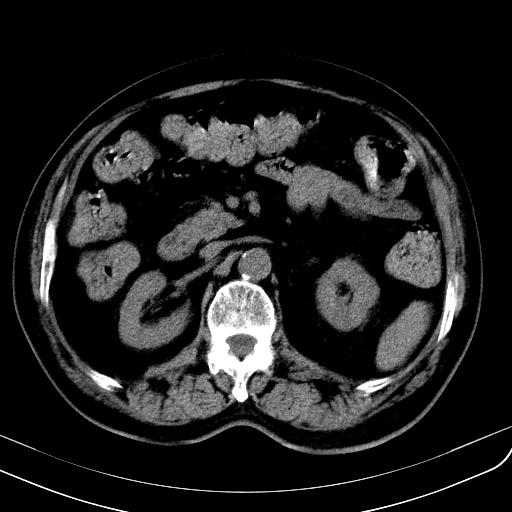

胃底靠近胃大弯处可见一圆形软组织影,直径为3.45cm,ct值约为30.1hu